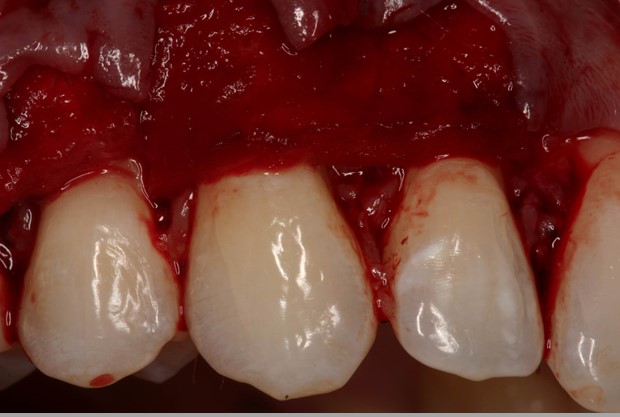

04/06 - The flap is repositioned in coronal direction to cover the root surfaces and the mucoderm® matrix completely.Multiple gingival recessions treated with the modified coronally advanced flap in conjunction with mucoderm® - Prof. Dr. Dr. A. Kasaj